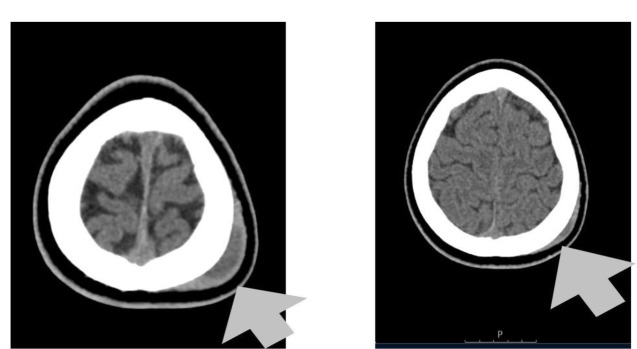

镰状细胞病是一种遗传性的血红蛋白形成疾病,主要影响非洲人、印度人或地中海后裔。由于镰状细胞阻塞小血管,导致组织梗死,这些患者经常发生急性疼痛发作。两名尼日利亚裔儿童在痛苦的危机发作期间出现严重头痛,并伴有头皮肿胀。两例病例的CT成像均显示galgala下血肿,除处理疼痛危机外,还进行了保守处理,结果良好。本报告重点介绍镰状细胞贫血这种罕见并发症的临床表现、诊断方法和治疗。

Sickle cell disease is an inherited disorder of haemoglobin formation, predominantly affecting individuals of African, Indian, or Mediterranean descent. Acute painful episodes frequently occur in these patients due to the blockage of small blood vessels by sickled cells, leading to tissue infarction. Two children of Nigerian descent, presented with severe headaches during a painful crisis episode with associated swelling on their scalps. CT imaging in both cases showed subgaleal haematoma which was managed conservatively in addition to managing the painful crisis with a good outcome. This report highlights the clinical presentation, diagnostic approach, and management of this uncommon complication of sickle cell anaemia.